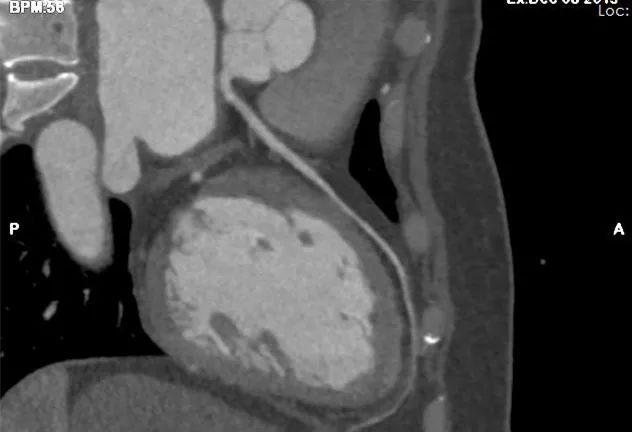

精准成像 心脏检查更精确

在心脏成像领域,高心率成像、支架术后再狭窄评估、冠脉钙化伪影及斑块成分分析等一直是困扰心血管临床治疗的难题。而CT通过SSF冠脉运动追踪冻结技术,不但可以解决上述困扰,更是填补了医院此类检查的空白。

近日,放射科相继完成了冠状动脉、颅内动脉、颈动脉、下肢动脉的CT扫描及三维成像处理,也陆续预约了其他部位动静脉的CT三维成像检查,开启了特殊三维成像业务的新篇章。